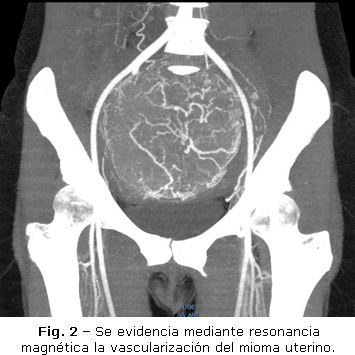

En la discusión con el colectivo médico se decidió preparar a la paciente para realizar embolización selectiva de las arterias uterinas. Previo al procedimiento se realizó resonancia magnética contrastada, en secuencias T1, T2 y técnica de supresión grasa, a fin de determinar la viabilidad del proceder (Fig. 2).